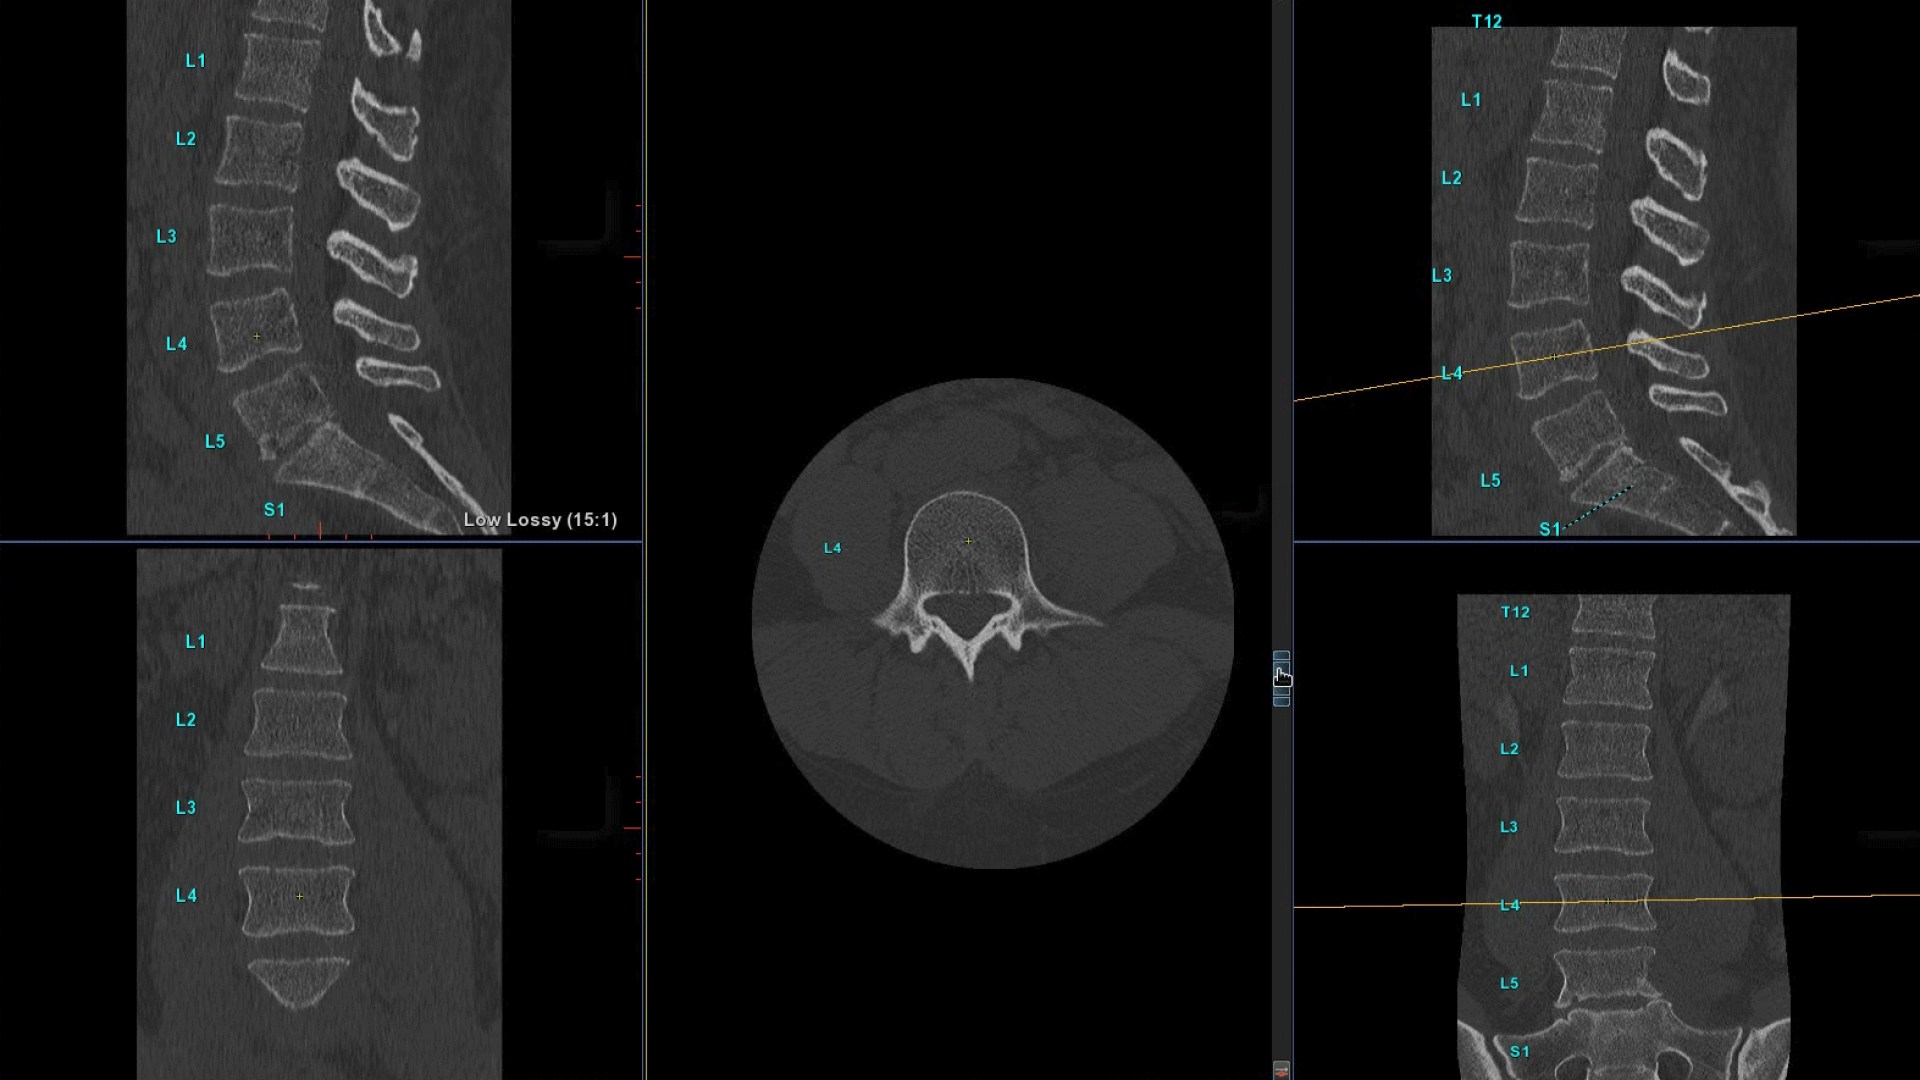

Bone VCAR

Spine assessment with deep-learning based CT application.

Automated spine identification and labelling.

>90% labeling accuracy based on Deep learning algorithm trained on global datasets acquired with a broad range of acquisition parameters.

• Automated spine labeling

• Automated generation of a 3D trace to generate oblique and straightened reformat views

• Automated generation of oblique views perpendicular to vertebral bodies and disc spaces

• Easily edit the centerline to ensure accurate placement in the most challenging cases

• Accessible for any exam type: trauma, oncology, dedicated spine, general imaging

• Load multiple series and vertebrae labeling will propagate to the different volumes

• Works on full spine acquisitions as well as limited acquisitions containing segments of the spine